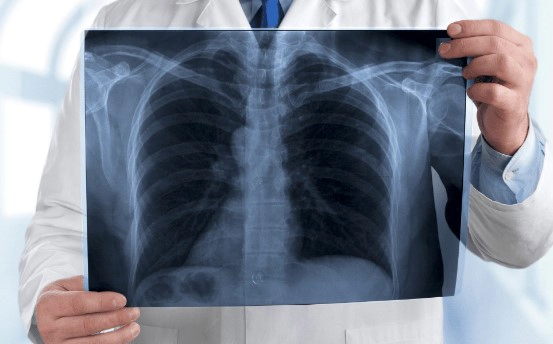

Q. 폐렴은 어떻게 진단되나요?

폐렴의 진단은 대체로 증상, 신체 진찰, 그리고 추가적인 검사를 통해 이루어집니다. 의사는 기침, 고열, 가슴 통증 등의 증상과 체온 측정, 심장 및 호흡 소리 청진 등의 신체 진찰을 진행할 것입니다. 또한, X-레이나 CT 스캔 같은 영상 진단, 혈액 검사, 가래 검사 등을 통해 확진을 내릴 수 있습니다.